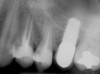

At the time of surgery, the tooth was extracted without harvesting any mucosal flap because the implant site was prepared by means of a pilot drill bur (Figure 13) and alternating osteotomes (Figure 14A and Figure 14B). The implant was positioned and showed primary stability. The implant was loaded 2 days after surgery. Then, splinted PFM crowns supported by custom gold abutments were delivered. At 6 months posttreatment, the radiograph revealed no bone resorption and the clinical result was optimal (Figure 15A and Figure 15B).

Figure 15 A Final implant-supported PFM restorations.

Figure 15B Posttreatment radiograph, 6 months after the initial surgery.